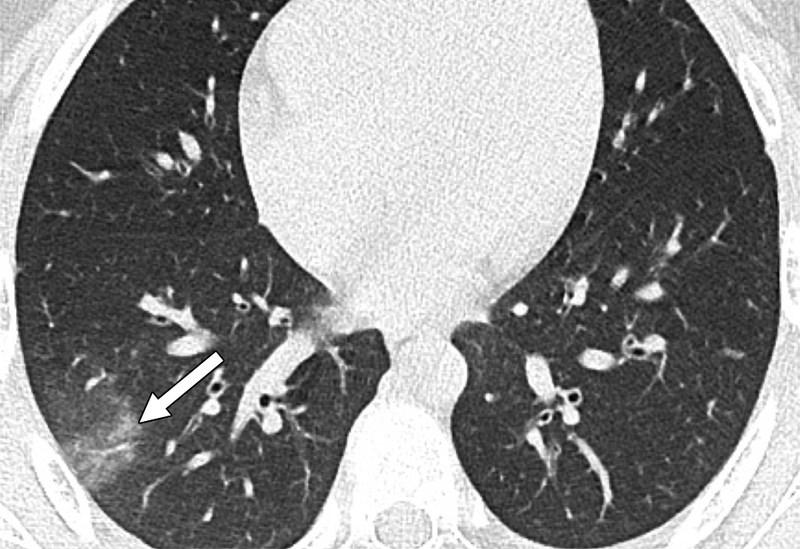

Μία εικόνα χίλιες λέξεις. Αξονικές τομογραφίες νέων κάτω από 18 έτη με Covid-19 (18 ετών, 15 ετών, 14 ετών και 8 ετών). Κανένας ασθενής δεν είχε υποκείμενα νοσήματα ή ανοσοκαταστολή. Οι ασθενείς δεν χρειάστηκαν συμπληρωματικό οξυγόνο, διασωλήνωση ή ΜΕΘ. Πρόκειται για απλά-κοινά περιστατικά Covid-19.

Ωστόσο έχουν πολύ “εντυπωσιακές” βλάβες και είναι άγνωστο τι θα προκαλέσουν αυτές οι βλάβες σε βάθος χρόνου. Για την πλειονότητα του κόσμου το ερώτημα είναι απλό: Θέλουν να υποβάλουν τους πνεύμονές τους σε αυτές τις βλάβες για να δουν αν αντέχουν; Και αν αντέξουν την πρόκληση (όπως προβλέπεται ότι θα αντέξουν οι περισσότεροι νέοι) θέλουν να δουν πόσα χρόνια ή αντοχές έχασαν στην πορεία; Με το εμβόλιο προστατεύουμε τους πνεύμονές μας από βαρύτατη καταπόνηση!